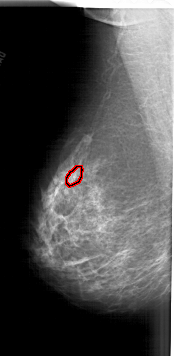

A_1905_1.RIGHT_CC

FILE: A_1905_1.LEFT_CC.OVERLAY

TOTAL_ABNORMALITIES 1

ABNORMALITY 1

LESION_TYPE CALCIFICATION TYPE PLEOMORPHIC DISTRIBUTION CLUSTERED

ASSESSMENT 4

SUBTLETY 3

PATHOLOGY MALIGNANT

TOTAL_OUTLINES 1

BOUNDARY